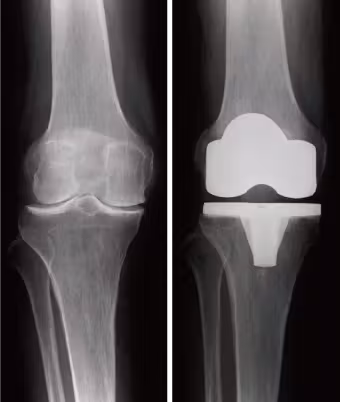

人工膝関節置換術は、虫歯に対するインプラント治療に似た治療法です。加齢に伴い傷んだ軟骨や変形した膝を元通りに戻すことはできませんので、人工関節に入れ替えることで痛みを取り除き変形を改善させる方法です。世界的にも多くの人工膝関節置換術が行われ、安定した長期成績が報告されています。しかし、ある一定頻度で感染、骨折、血栓症などの合併症が生じることも事実です。できるだけ合併症なく手術が受けていただけるように、努力を続けていきたいと思います。

人工膝関節置換術